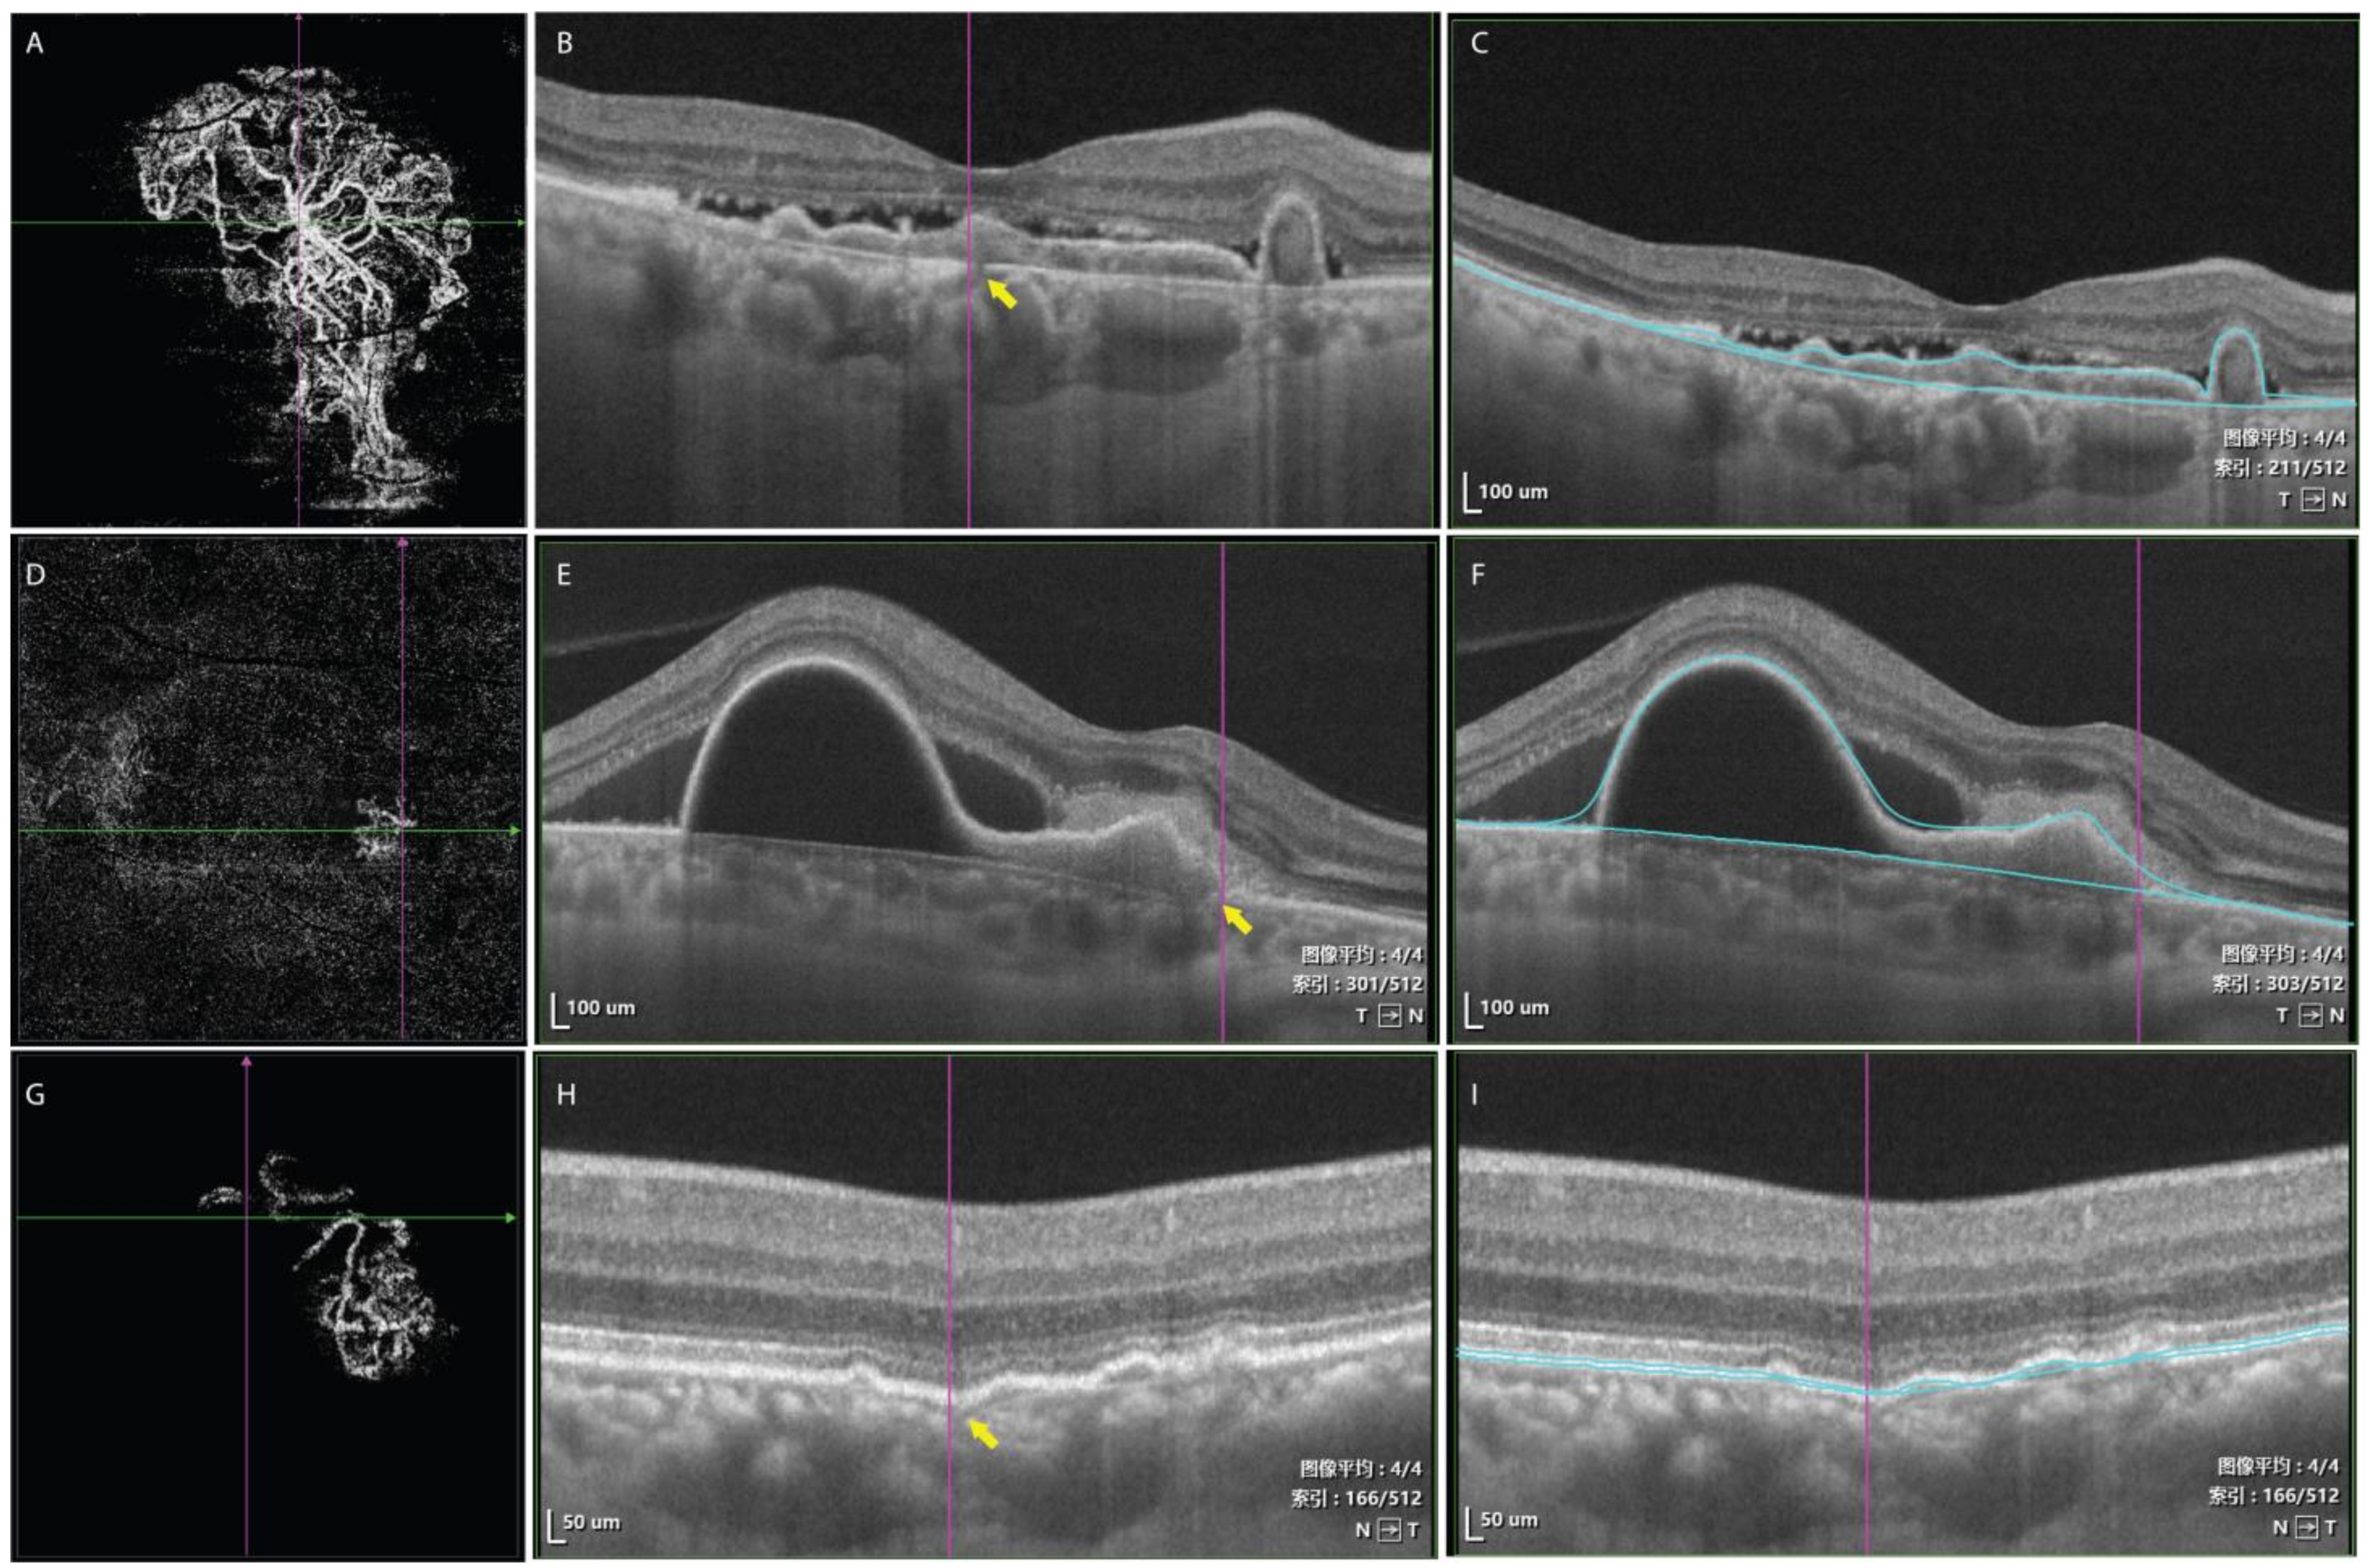

- Huang, C.H.; Yeh, P.T.; Hsieh, Y.T.; Ho, T.C.; Yang, C.M.; Yang, C.H. Characterizing Branching Vascular Network Morphology in Polypoidal Choroidal Vasculopathy by Optical Coherence Tomography Angiography. Sci. Rep. 2019, 9, 595. [Google Scholar] [CrossRef]

- Ma, S.T.; Huang, C.H.; Chang, Y.C.; Lai, T.T.; Hsieh, Y.T.; Ho, T.C.; Yang, C.M.; Cheng, C.G.; Yang, C.H. Clinical features and prognosis of polypoidal choroidal vasculopathy with different morphologies of branching vascular network on optical coherence tomography angiography. Sci. Rep. 2021, 11, 17848. [Google Scholar] [CrossRef]